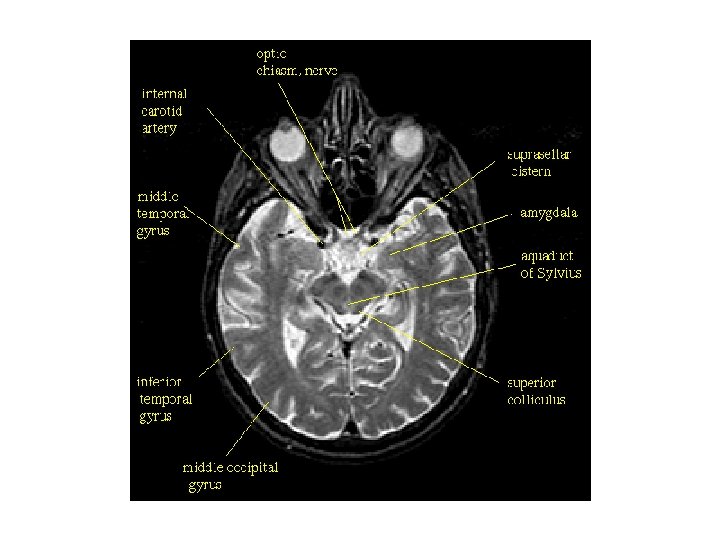

대뇌 기저표면에서 관찰되는 구조 1. 후각망울(olfactory bulb, 후각구) 3. 곧은이랑(rectus gyrus, 직회) 5. 후각삼각(olfactory trigone, 후삼각) 2. 후각로(olgfactory tract, 후삭) 4. 안와이랑(orbital gyrus, 안와회) 6. 시각신경교차(optic chiasm, 시신경교차) 7. 전관통질(anterior perforating subsance, 전유공질) 9. 편도체주위피질(periamygdaloid cortex, 반월이랑 gyrus semilunaris) 11. 갈고리이랑(uncus, 구) 8. 주위이랑(gyrus ambience) 13. 해마옆이랑(parahippocampal gyrus, 해마방회) 14. 중뇌(midbrain) 15. 혀이랑(lingual gyrus, 설상회) 16. 후두측두이랑(occipitotemporal gyrus, 후두측두구) 17. 19. 21. 23. 25. 18. 20. 22. 24. 26. 측면고랑(collateral sulcus, 측부구) 유두체(mammillary body) 시각로(optic tract, 시삭) 외측후각선조(lateral olfactory striae) 시각신경(optic nerve, 시신경) 10. 내후각뇌피질(entorhinal cortex, 내후뇌피질) 12. 후관통질(posterior perforating substance, 후유공질) 하전두이랑(inferior frontal gyrus) 후각뇌고랑(rhinal sulcus, 후뇌구) 내측후각선조(medial olfactory striae) 외측고랑(lateral sulcus, 외측구) 후각고랑(olfactory sulcus, 후구)